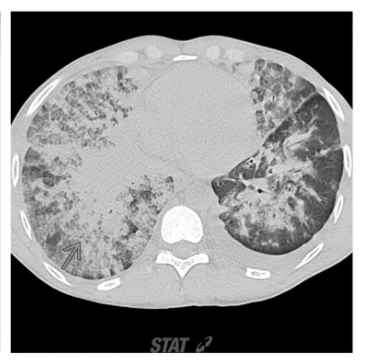

What CT findings are typical for segmental/bronchopneumonia

• Multifocal patchy consolidation of secondary lobules with no air bronchogram

• Can also have ground glass opacity and thickened bronchial opening